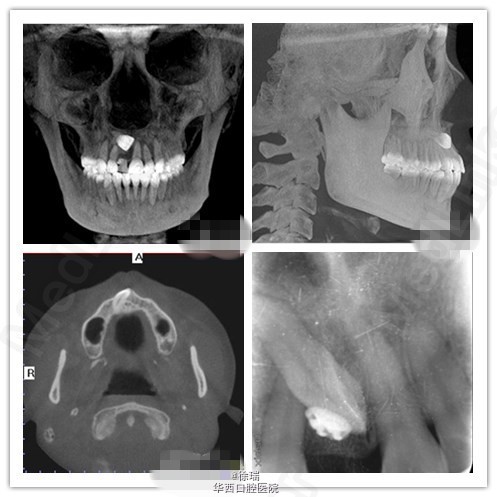

“逆天”的中切牙

前几日看到一个病例,高位阻生的中切牙,有牵引向下的指征,但正畸治疗几个月后,患者忽然不同意做正畸治疗了。遇到这样的情况,大家觉得该如何处理呢?